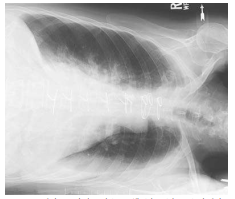

What projection/position is this?

Left Lateral Decubitus (AP)